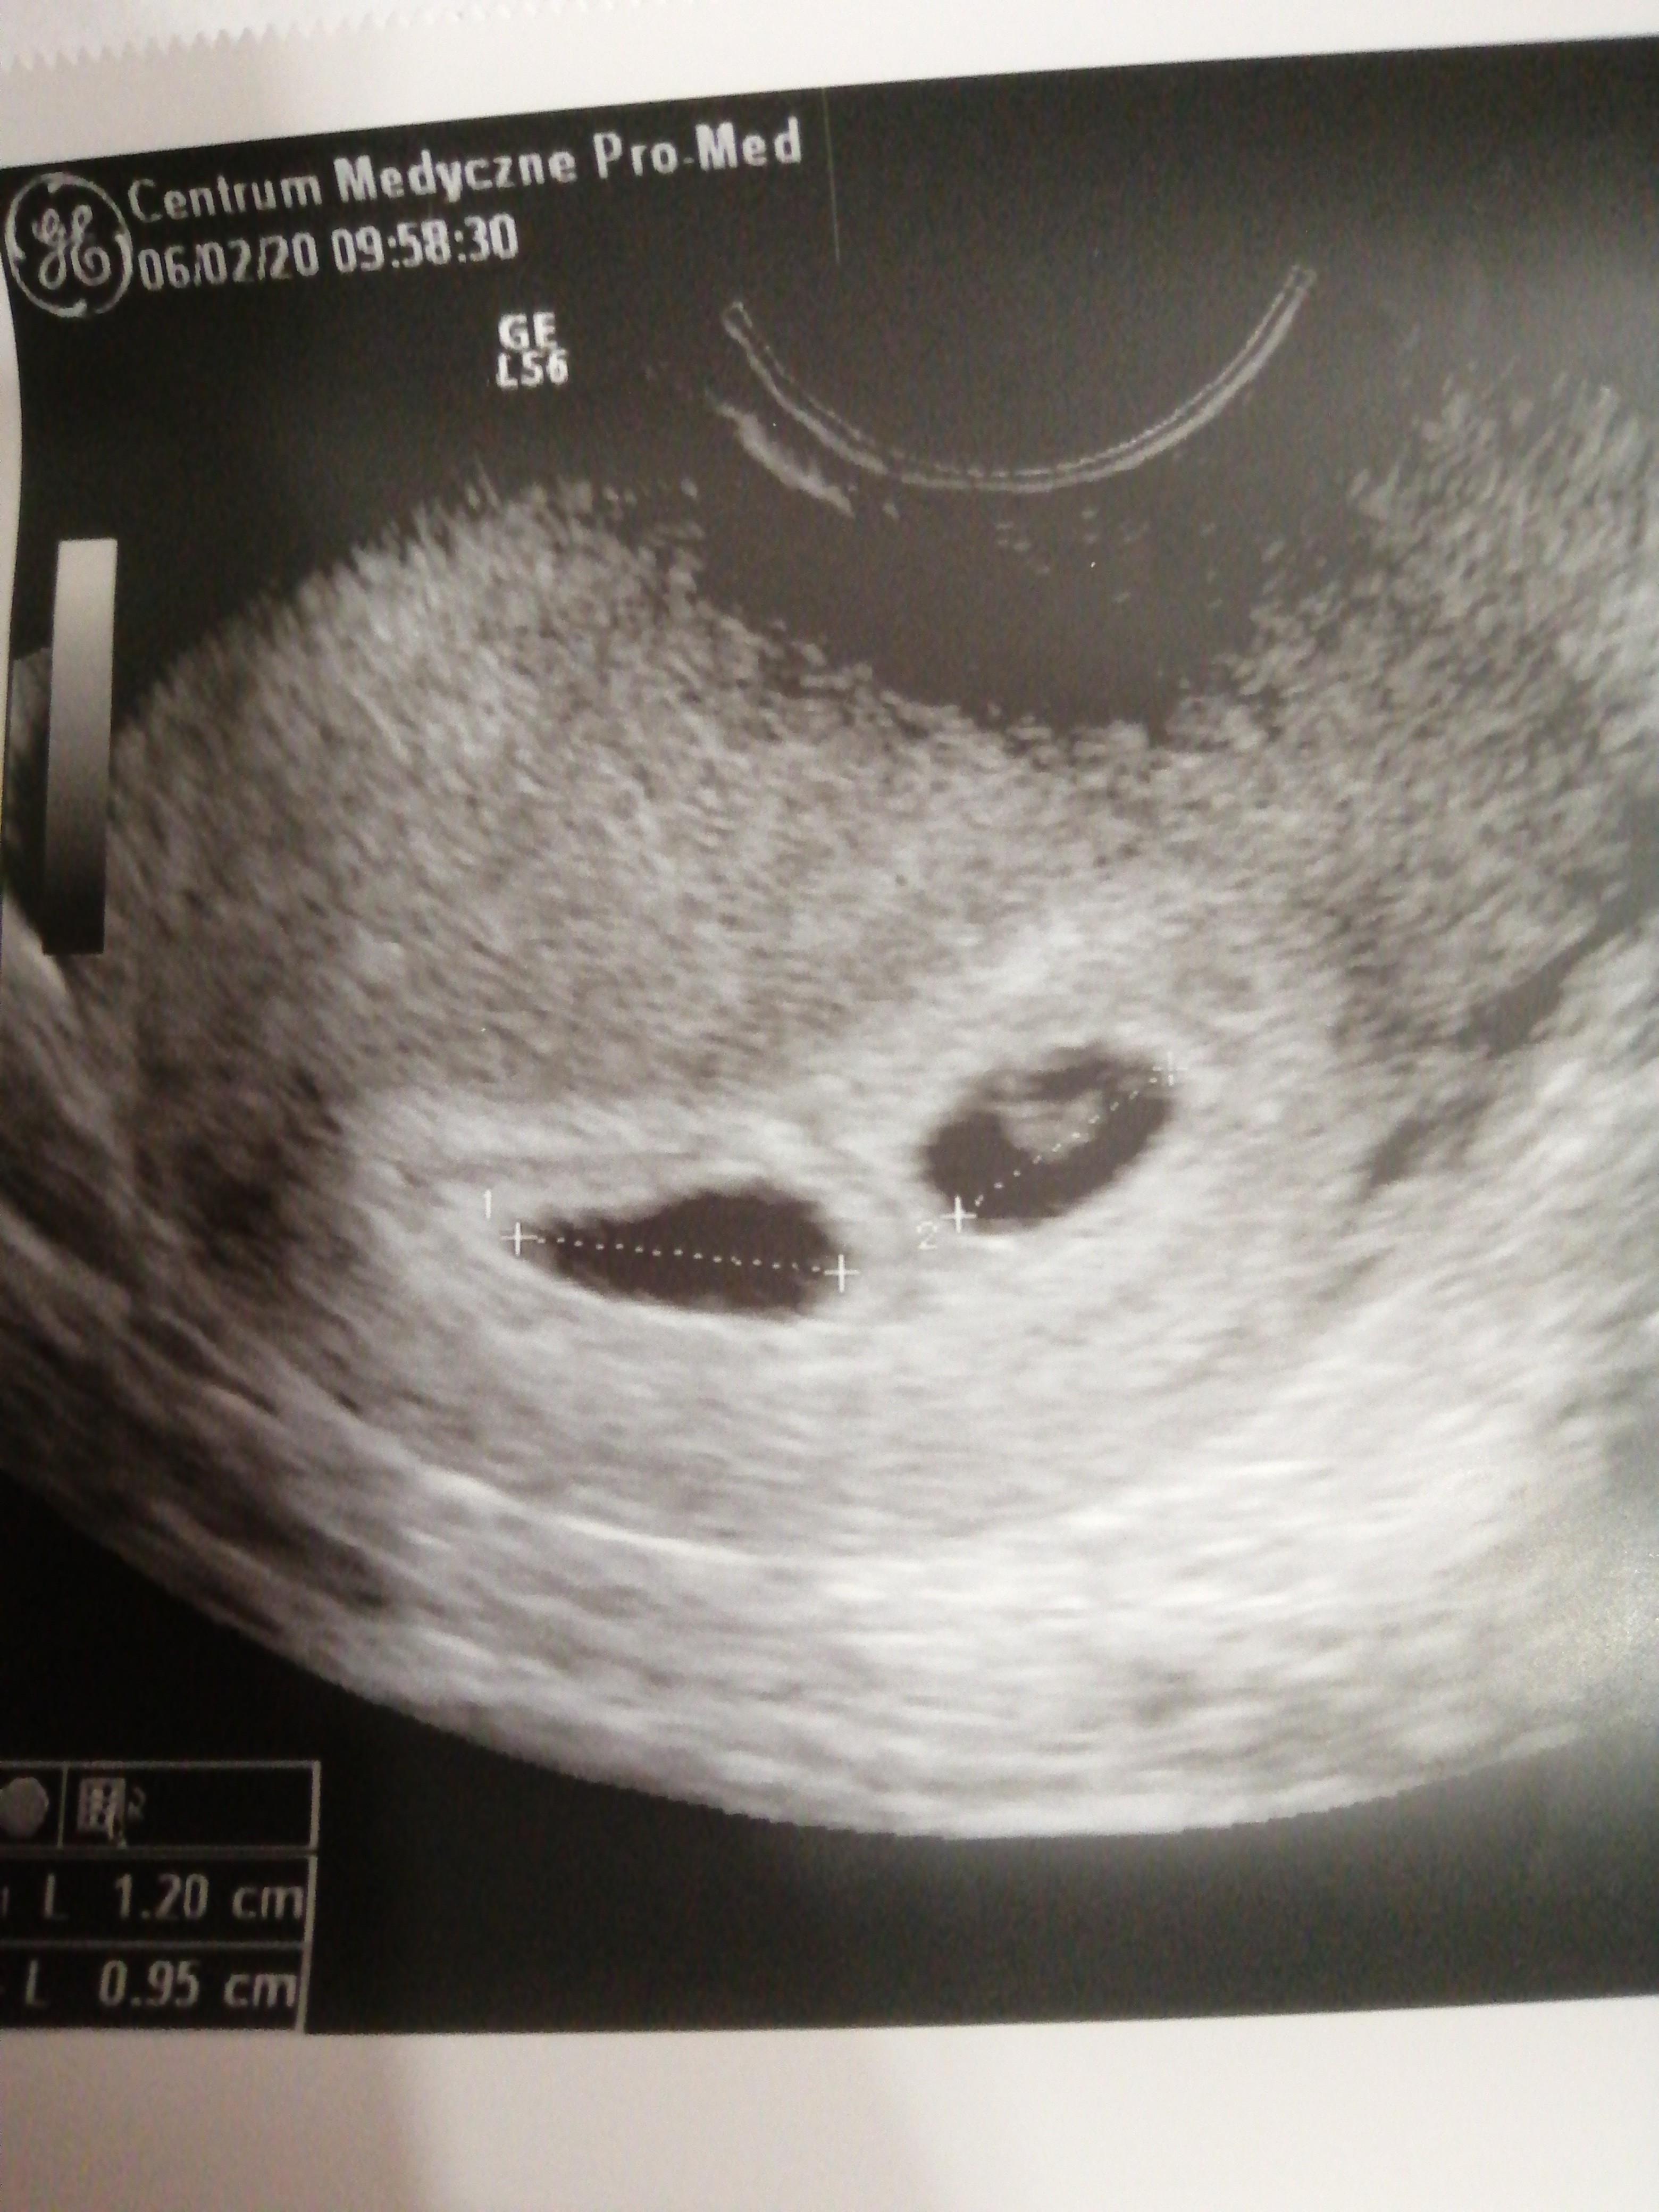

GratulujęHej. Ja po wizycie i usg. Poszłam tak wcześnie (5t+1) bo strasznie mnie boli i ciągnie brzuch. A jestem po jednym poronieniu.

No i..... okazało się że tak źle się czuję bo mam 2 pęcherzyki plodowe. Za 2tyg ponowna wizyta i zobaczymy czy będzie jedno czy bliźniakiZobacz załącznik 1076875